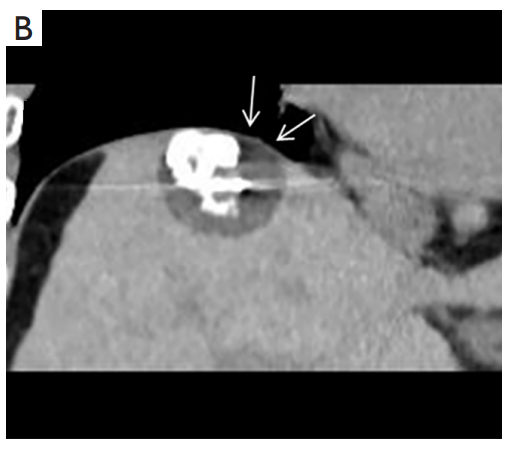

背景:肝癌是中國最常見的惡性腫瘤之一,發病率和死亡率都很高。雖然手術切除是最好的治療方法,但大多數患者處于晚期或直到住院才有手術指征。對于單個腫瘤直徑小于5厘米的患者,微創治療與手術切除效果相當;多個病灶小于3個,單個病灶最大直徑小于3cm;不侵犯血管、膽管、鄰近器官和遠處轉移。雖然一些傳統消融技術方式可以使部分患者受益,但不適用于特殊部位肝癌(定義為毗鄰大血管、肝外臟器和重要結構的腫瘤)的治療。冷凍消融作為一種相對較新的治療方式,具有明顯的冰球效果、療效好、激活抗腫瘤免疫、并發癥發生率低等優點,尤其適用于特殊部位肝癌患者的治療。我們的研究目的是探討CA治療特殊部位肝癌的安全性、可行性和有效性。

① 在我們的研究中,技術成功率為100%。動態增強MR檢查隨訪1個月,66例患者首次技術有效率為65例(98.5%),MR影像學未發現外周臟器損傷。中位隨訪時間14個月(范圍2-28個月)。高危部位肝癌局部腫瘤進展率曲線:6、9、15和24個月的累積局部腫瘤進展率分別為10.2%、16.5%、20.9%和30.5%。